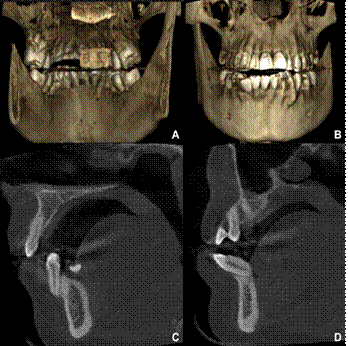

En ocasiones, la versión canina, es inapreciable y es el incisivo el que muestra una versión radiculovestibular o coronovestibular muy marcada (8. En algunos casos, también los incisivos están desalineados y sus ejes inclinados junto con el canino comprometido, como se puede ver en la figura 2 y 3. En otros casos, donde la contención fue colocada solamente en los incisivos inferiores, son estos los que sufren los movimientos como se puede ver en la figura 4.